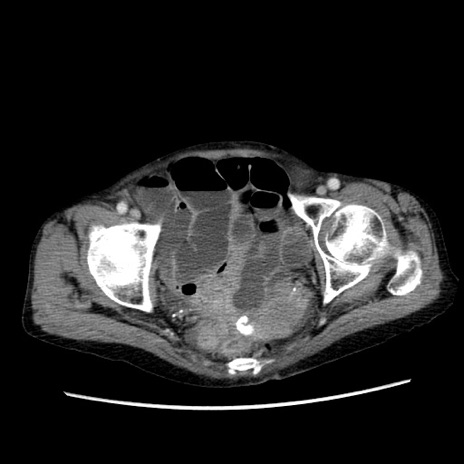

症例25(横断像)

【症例】80歳代女性

【主訴】胸のつかえ感

【現病歴】約9時間前に食後から胸のつかえた感じあり、嘔吐あり、来院。

【既往歴】胃癌(全摘)、胆摘、虫垂炎

【身体所見】心窩部に圧痛あり、反跳痛なし。

【データ】WBC 5700、CRP 0.05